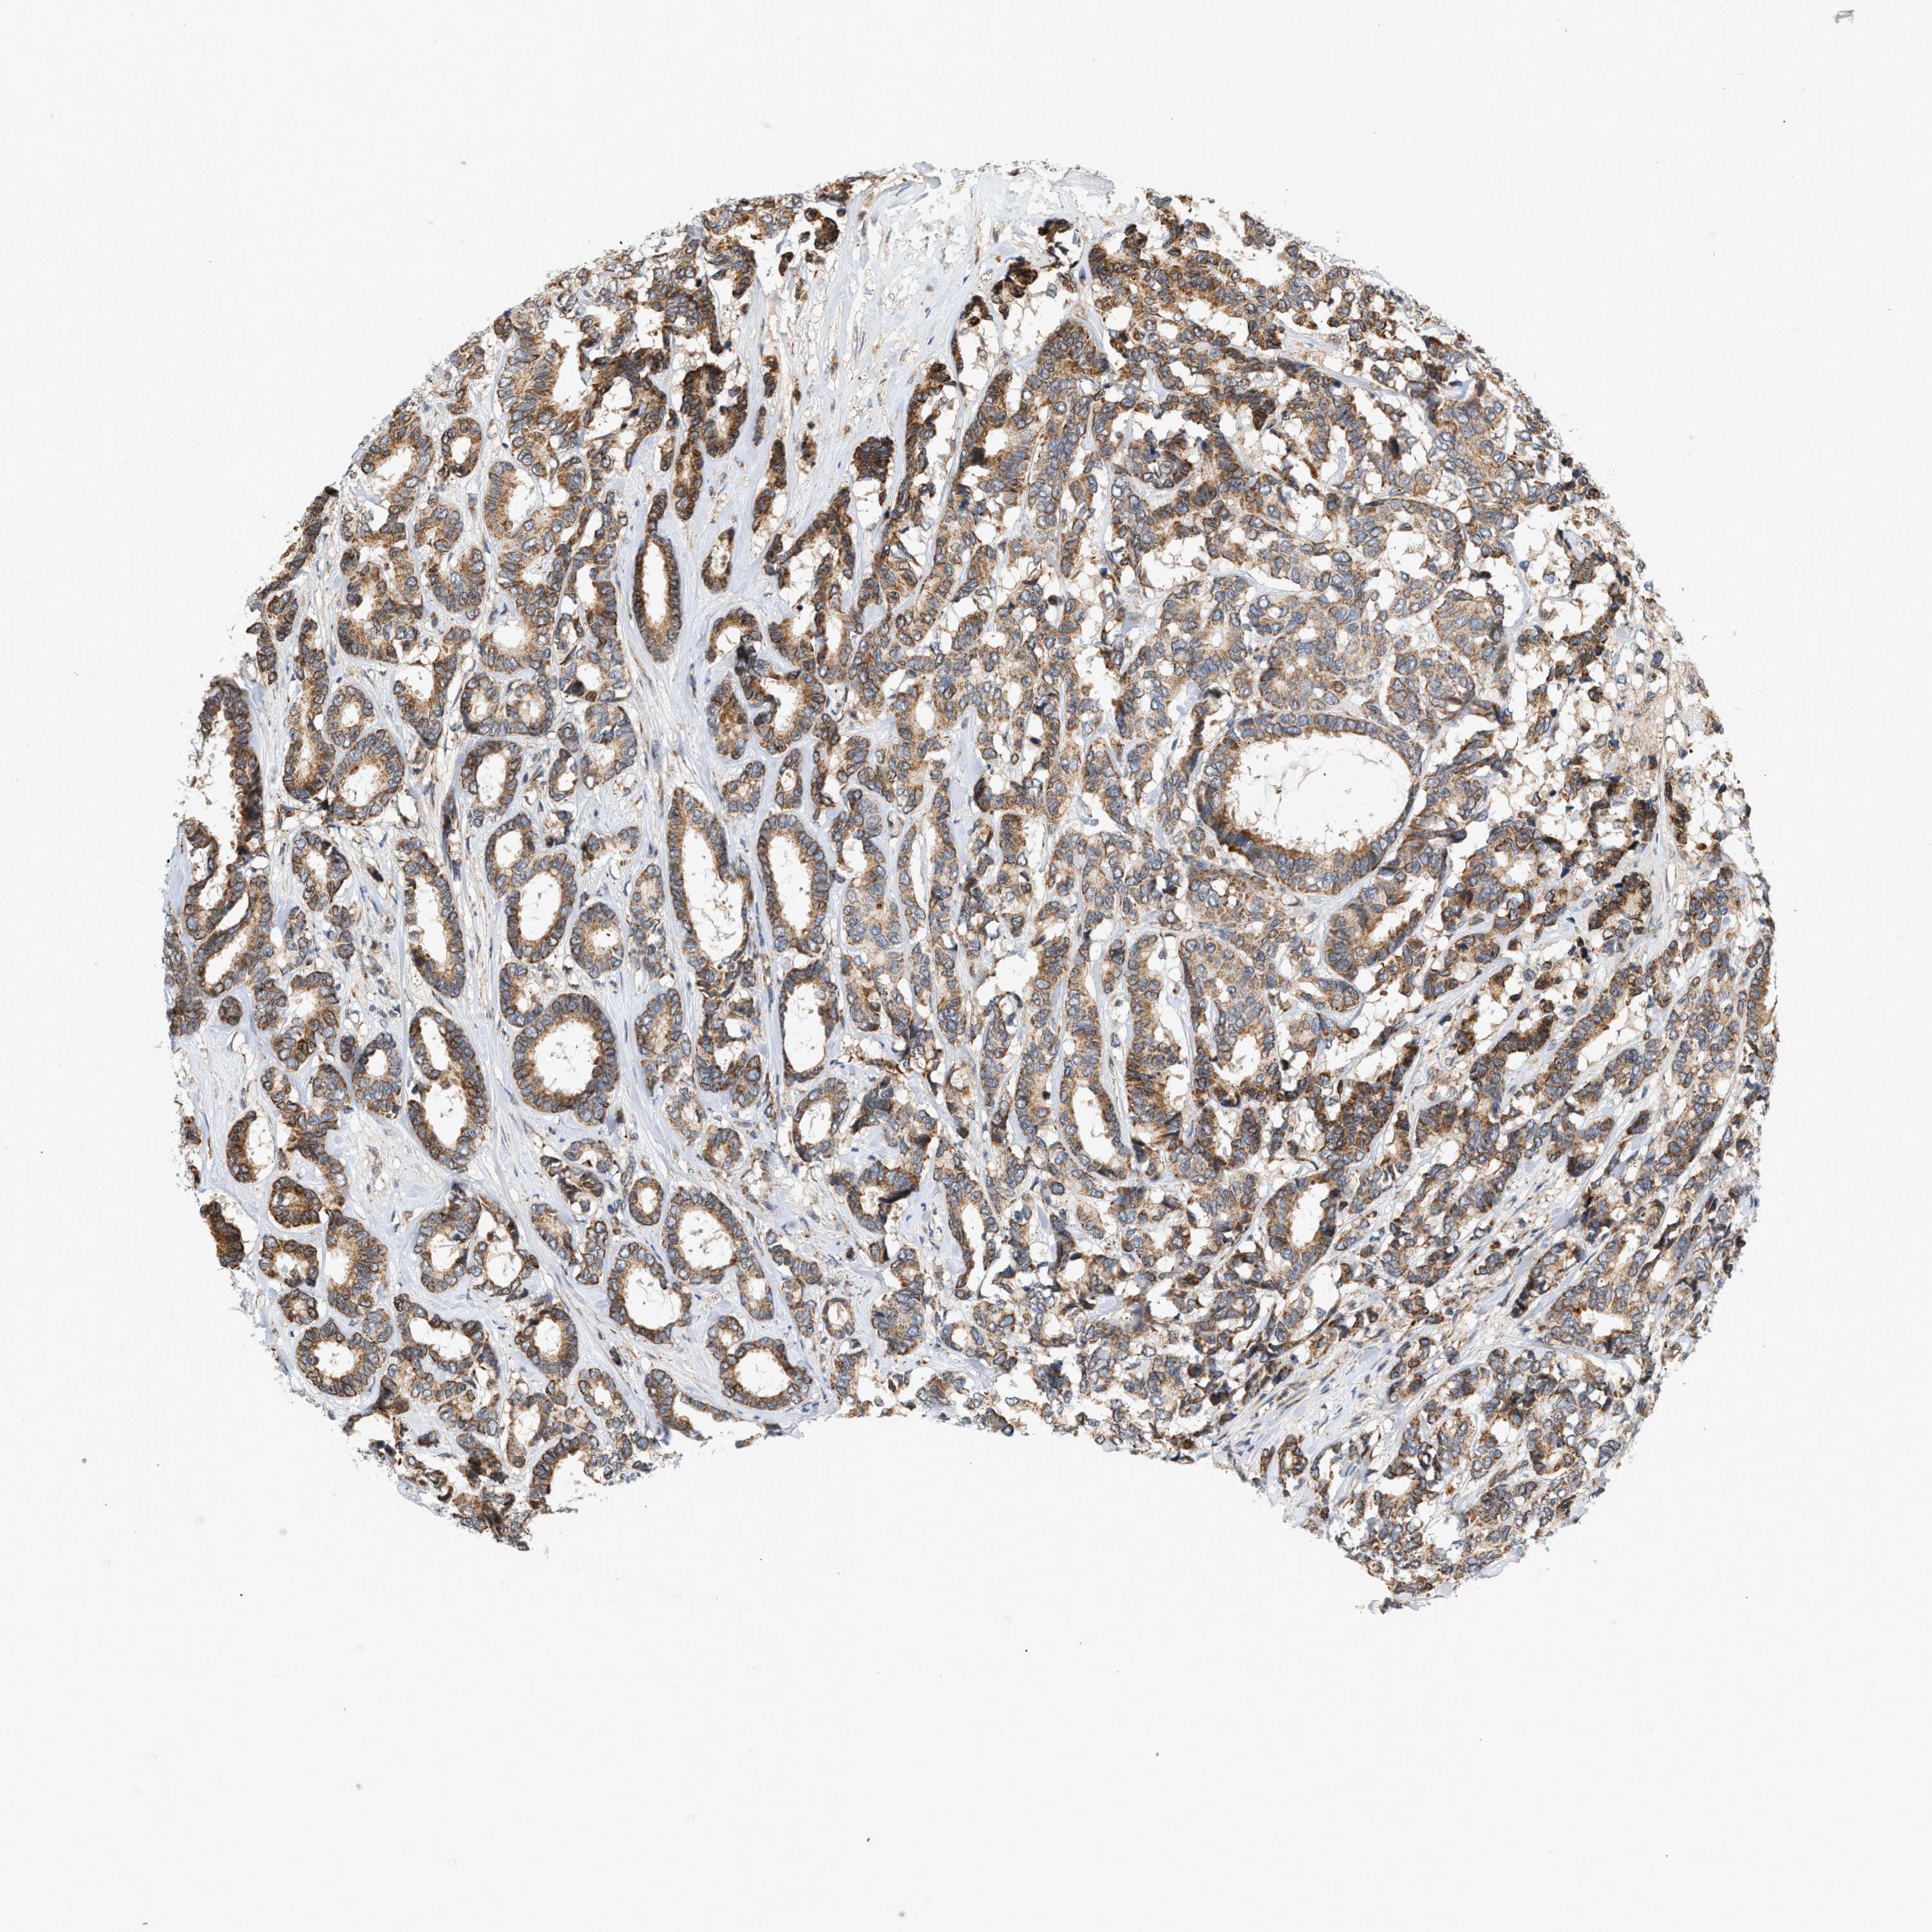

CANCER BREAST CANCER Show tissue menu

BRCA TCGA BRCA VALIDATION PROTEIN EXPRESSION